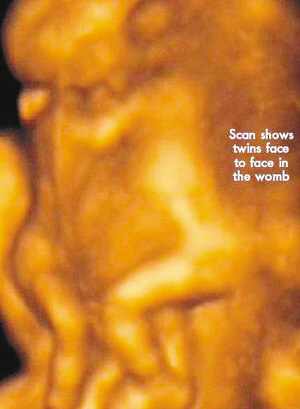

今年初,懷孕7周多的麗莎檢查發(fā)現(xiàn),懷上的竟是一對腹部緊緊相連的連體男嬰。這對連體嬰共享一只肝臟,雖然他們擁有各自的心臟,但兩顆心臟卻粘連在了一起。醫(yī)生建議麗莎立即接受流產(chǎn)手術(shù),他認為麗莎腹中的連體嬰甚至無法活到她懷孕10周的時候。

麗莎每周都要到醫(yī)院接受醫(yī)學(xué)掃描,而她腹中的連體嬰也讓醫(yī)生感到驚訝不已,因為他們已經(jīng)打破了醫(yī)生的死亡預(yù)言,一直在母親子宮中堅強活到了現(xiàn)在。麗莎將于兩周內(nèi)接受剖腹產(chǎn)手術(shù)。